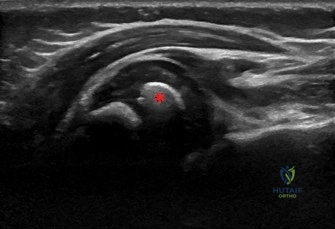

MRI Findings (Cervical Spine and Brachial Plexus, T1 and T2 weighted sequences with fat suppression):

* Sagittal and Axial T2-weighted images: Demonstrated T2 hyperintensity and thickening of the right C5 and C6 nerve roots in the supraclavicular fossa, consistent with significant stretch injury and edema, likely representing neuromas-in-continuity or ruptures.

* No clear evidence of pseudomeningoceles in the cervical spinal canal, which reduces the likelihood of complete preganglionic C5/C6 avulsion, but does not definitively rule it out.

* The C7, C8, and T1 nerve roots appeared to be structurally intact, with normal signal intensity and caliber.

* The overall architecture of the cervical spinal cord and vertebral bodies was normal.

* No significant paraspinal hematoma or other soft tissue abnormalities were observed.

Interpretation: The MRI findings suggested a severe postganglionic injury to the C5 and C6 nerve roots, either a complete rupture or a neuroma-in-continuity, rather than a definitive preganglionic avulsion. This information is crucial for determining the potential for nerve repair (grafting) versus nerve transfer.

Figure 1: Representative MRI image (T2-weighted sagittal view) of a brachial plexus, illustrating typical findings such as T2 hyperintensity and thickening indicative of neuroma-in-continuity (not specific to this patient, but illustrative of a common finding in BPBP).